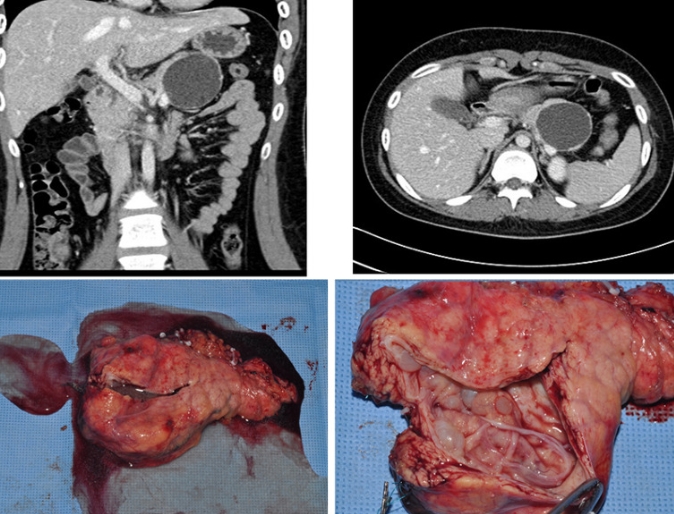

복부 전산화단층촬영(CT)은 현재까지 췌장암을 초기에 진단하는 데 가장 적합한 방법으로 꼽힌다. 검사자의 숙련도에 따라 결과 정확도가 달라지는 복부초음파의 단점을 보완하면서, 크기가 비교적 작은 암도 발견할 수 있다는 점이 강점이다. 병변을 조영제(혈관에 주입해 더 선명한 영상을 얻는 약물)와 함께 촬영하면 암의 위치, 크기, 주변 혈관 침범 여부까지 한 번에 파악할 수 있다.

췌장암 검사방법 비용 중 CT는 급여 적용 시 가장 접근하기 쉬운 편이다. MRI(자기공명영상)는 방사선 노출이 없고, 담관(쓸개즙이 지나는 관)·췌관(췌장에서 소화액이 흐르는 관) 관찰이나 간 전이 여부 확인에서 CT보다 더 정밀하다는 평가를 받는다. 검사 시간이 길고 숨을 오래 참아야 하며 비용 부담이 더 크기 때문에, CT에서 결과가 애매하거나 추가 정보가 필요할 때 병행하는 흐름이 일반적이다.